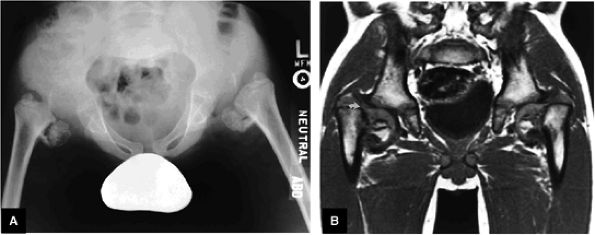

Classification of DDH is based on the configuration of the acetabulum and labrum.

Identification of the capital epiphysis location requires both coronal and axial images.

In mild DDH, anterior coronal MR images display an increased slope of the acetabulum.

DDH in the young adult may be associated with acetabular labral pathology and acetabular rim syndrome.

casts or with equivocal conventional radiographs.110,111 The sector angle should be used to evaluate acetabular coverage (from the capital epiphysis to acetabular rim relative to the horizontal axis).

Supralateral subluxation or dislocation is best identified on coronal MR images, and AP relationships and dysplasia of the acetabular wall are best demonstrated on axial plane images.

The coronal plane is the most useful for evaluating acetabular labral coverage beyond the lateral margin of the bony acetabulum relative to the femoral capital epiphysis (see Fig. 3.100). This is important in determining the coverage of the femoral head and the possible need for increased coverage through surgical osteotomy. If adequate coverage is provided by the bony acetabulum and acetabular labrum together, more conservative management of DDH may be appropriate.

FIGURE 3.100 ● DDH. (A) Pseudo-coverage of the capital epiphysis by an everted labrum. Coronal radiograph (B) shows complete lateral uncovering of the femoral capital epiphysis associated with a shallow acetabulum. A corresponding T2* coronal MR image (C), however, demonstrates improved coverage by a mildly deformed but primarily everted labrum (arrows).

FIGURE 3.101 ● (A) DDH associated with longitudinal tearing of a hypertrophied labrum. The shallow slope of the acetabulum is demonstrated. The transverse angle of the osseous acetabular rim affects the degree of lateral coverage and is increased in adult DDH. (B) The normal angle of 40° is shown in contrast to (A).